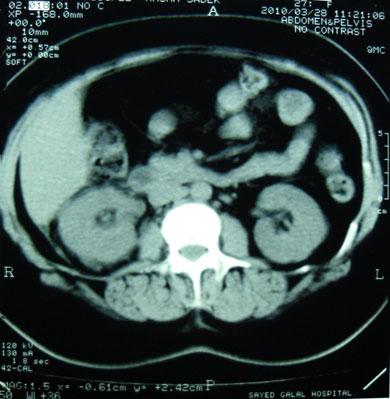

Chronological Photo-sequence

of the case progression

-On presentation: